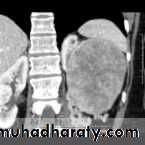

Renal S.O.L (cyst)

RENAL CYST

IVU :-* Nephrogram shows filling defect .

*Displacement , elongation & stretching of PCS which depend on size and site of the cyst .